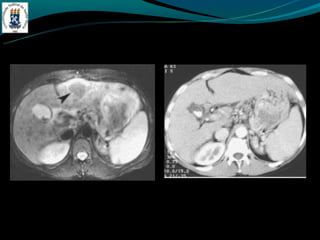

- TC: hepatomegalia heterogênea, não visualização das veias

hepática, ascite, realce hepático central, lobo caudado preservado

ou aumentado.

BUDD-CHIARI -Hipercoagulabilidade -Compressão – tumor -Membranada VCI -Dor abdominal, hepatomegalia e ascite. - TC: hepatomegalia heterogênea, não visualização das veias hepática, ascite, realce hepático central, lobo caudado preservado ou aumentado.